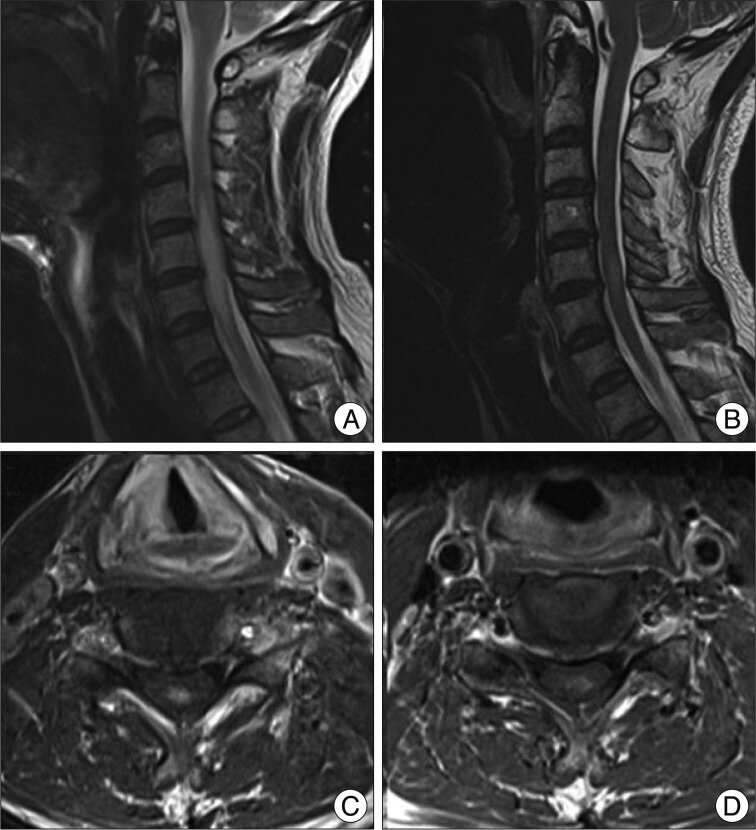

- 脊髄 MRI において、頸部~胸部に限局した白質・灰白質内の病変を認める例があります。 J-STAGE+1

- MRI で脊髄の限局病変を認め、髄液検査では特異的所見を欠くことが多い。 PubMed+1

- MRIでは**頸髄または胸髄に限局した高信号域(T2強調像)**を認める。

- 治療後に病変が縮小・消失する例が多い。

- 髄液所見は正常〜軽度蛋白増加で、慢性多発性硬化症とは異なる。